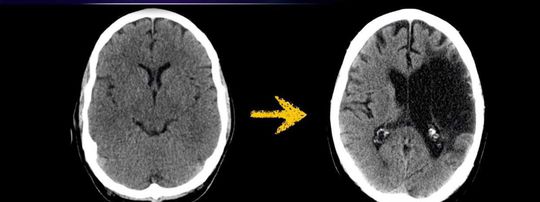

Ischemic stroke ( CVA ) is characterized by the sudden loss of blood circulation to an area of the brain, resulting in a corresponding loss of neurologic function. Acute ischemic stroke is caused by thrombotic or embolic occlusion of a cerebral artery and is more common than hemorrhagic stroke.